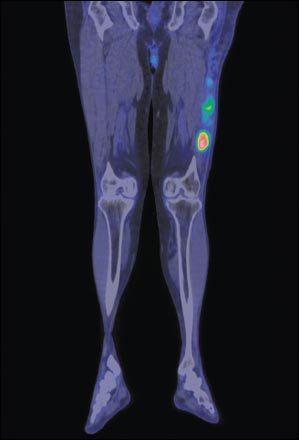

FDG-PET/CT fusion image of the legs, frontal section, showing liposarcoma of the left thigh. Liposarcoma is a malignant tumor that develops in deep soft fatty tissue.